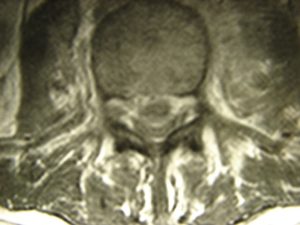

Ο μετεγχειρητικός έλεγχος δια Μαγνητικής Τομογραφίας, Ακολουθία Τ1 και Τ2 έδειξε την αποσυμπίεση των νευρικών στοιχείων.

Εικόνα 6 (α,β,γ,δ)

Οβελιαία τομή (α,β)Παρατηρείται η αποκατάσταση της συνέχειας του νωτιαίου σάκου και το άδειασμα των προ-παρασπονδυλικών αποστημάτων και επισκληριδίου αποστήματος.

Εγκαρσία τομή (γ,δ)Είναι εμφανής η αποσυμπίεση του νωτιαίου σάκου και η φλεγμονώδης αντίδραση του προσβεβλημένου μεσοσπονδυλίου δίσκου και των προ-παρασπονδυλικών μαλακών μορίων.